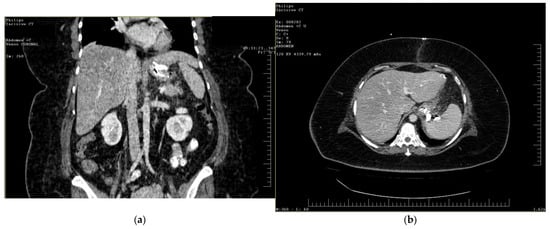

The postoperative course remained favorable (Figure 4 and Figure 5), allowing the medical team to discharge the patient after 51 days with specific recommendations.

Figure 4.

Contrast-enhanced abdominal radiograph demonstrating complete resolution of the fistulous tract, with no contrast leakage or communication visible.